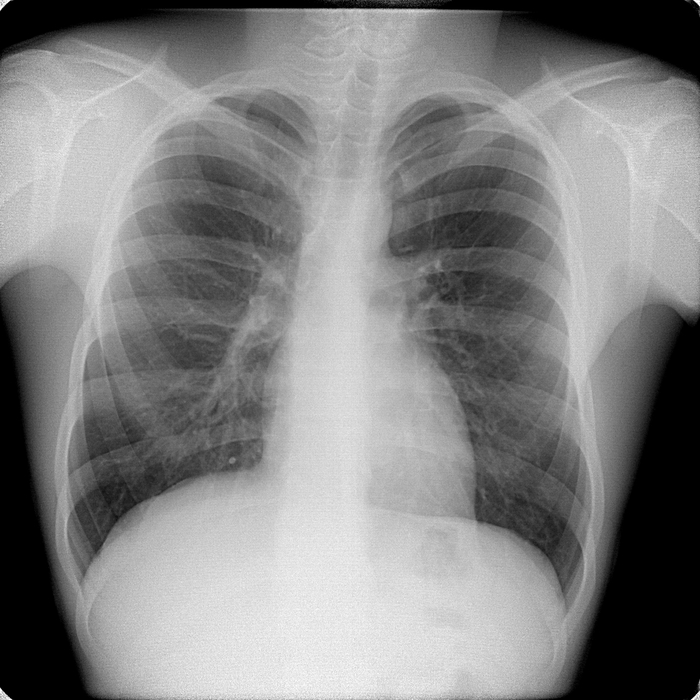

Расшифровка цифровых кодов флюорографии с примерами

01 - Кольцевидная тень (полость).

02 - Затемнение в легочной ткани (инфильтрация,ателектаз, округлая тень, среднедолевой синдром и др.).

03 - Очаговые тени в легочной ткани.

04 - Расширение тени средостения, в том числе увеличение размеров корня.

05 - Плевральные выпоты.

06 - Фиброзные изменения в легочной ткани (выраженные).

07 - Фиброзные изменения в легочной ткани (ограниченные).

08 - Повышение прозрачности легочной ткани (эмфизема локальная и распространенная).

09 - Изменения плевры (сращения, плевральные наслоения, обызвествления) выраженные.

10 - Изменения плевры (сращения, плевральные наслоения, обызвествления) ограниченные.

11 - Петрификаты крупные в легочной ткани - множественные (5 и более).

12 - Петрификаты крупные в корнях - множественные (5 и более).

13 - Петрификаты мелкие в легочной ткани - множественные (5 и более).

14 - Петрификаты мелкие в корнях - множественные (5 и более).

15 - Петрификаты крупные в легочной ткани - единичные.

16 - Петрификаты крупные в корнях - единичные.

17 - Петрификаты мелкие в легочной ткани - единичные.

18 - Петрификаты мелкие в корнях - единичные.

19 - Изменения диафрагмы, не связанные с плевральной патологией (диафрагмальная грыжа, высокое стояние диафрагмы и т. д.).

20 - Состояние после операции на легком.

21 - Изменения скелета грудной клетки (сколиоз, кифосколиоз, костная мозоль, добавочное ребро, остеофиты и т. д.).

22 - Инородное тело (проецируется на легочную ткань, тень средостения в мягких тканях).

23 - Сердечно-сосудистая патология.

24 - Прочие - добавочная доля.

25 - Норма.

26 - Брак.

Примечания:

При сочетании нескольких из перечисленных изменений каждое из них отмечается соответствующим кодом в каждой графоклетке.

Локализация, протяженность изменений отмечается дробью по второй графоклетке 1; 2; 3; 4; в числителе - правое легкое, в знаменателе - левое легкое (по полям).

Номер шифра легочных полей: 1 - первое, 2 - второе, 3 - третье, 4 - первое и второе, 5 - первое и третье, 6 - второе и третье, 7 - первое, второе и третье.

В третьей графоклетке вместо подписи врача подставляют личный номер рентгенолога.

Вызов на контрольное рентгеновское дообследование отмечается в четвертой графоклетке цифрой 1.